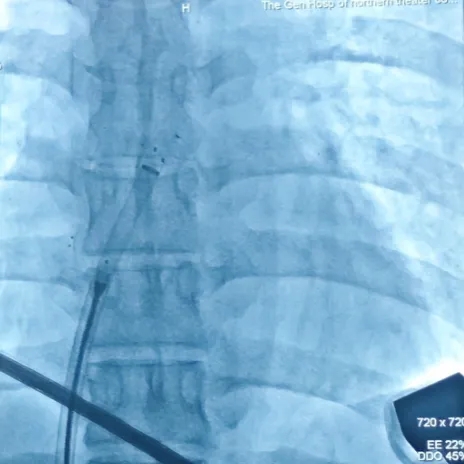

导丝过隔

送入输送鞘,撤出导丝

左盘展开

DSA下,左盘面3个Mark点聚拢

超声下左盘贴壁

锁定封堵器

封堵器成型,DSA下可见4个Mark点聚拢

锁定后牵拉实验

轻轻牵拉钢缆,4个Mark点依然聚拢在一起

Mark点相对位置未发生变化,并随着钢缆摆动

释放封堵器

钢缆和鞘管同时撤出,成功释放封堵器